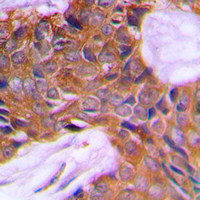

IHC (Immunohiostchemistry)

(Dilution: WB: (1/500 - 1/1000), IH (1/100 - 1/200)Immunohistochemical analysis of PAGE3 staining in human prostate cancer formalin fixed paraffin embedded tissue section. The section was pre-treated using heat mediated antigen retrieval with sodium citrate buffer (pH 6.0). The section was then incubated with the antibody at room temperature and detected using an HRP conjugated compact polymer system. DAB was used as the chromogen. The section was then counterstained with haematoxylin and mounted with DPX.)